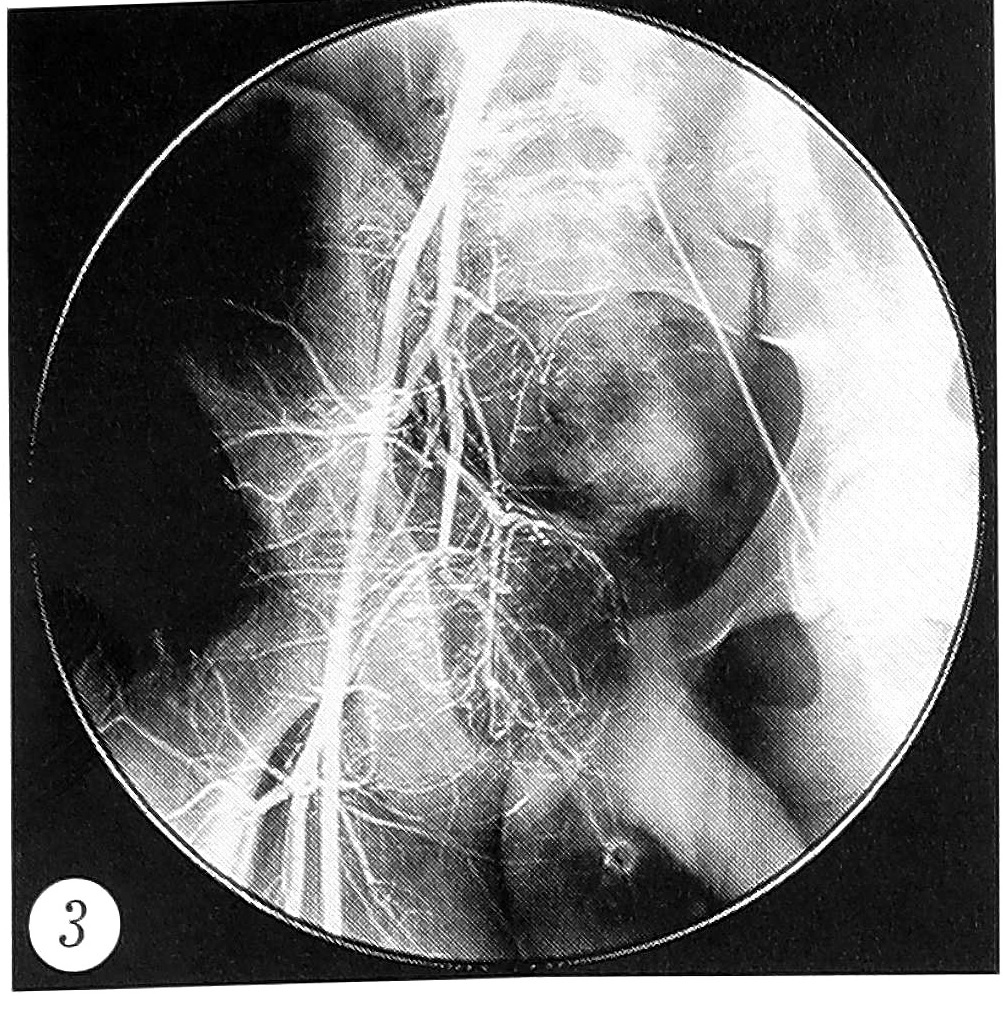

Принимая во внимание резкую отрицательную клинико-рентгенологическую динамику заболевания, а также его доброкачественную природу, было решено произвести хирургическое вмешательство. С учетом ожидаемой массивной кровопотери перед операцией выполнена ангиография для выявления питающего очаг сосуда и его последующей временной окклюзии с целью уменьшения кровотечения во время операции. Обнаружено, что питание очага осуществляется из бассейна внутренней подвздошной артерии, очаг состоит из четырех узлов, обильно кровоснабжаемых патологической сетью сосудов (рис. 3).

Рис. 3. Предоперационная ангиограмма: кровоснабжение очага из бассейна внутренней подвздошной артерии.